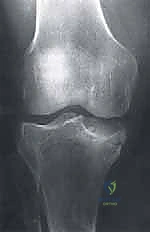

2. التصوير بالأشعة السينية (X-rays)

هي الخطوة التصويرية الأولى والأساسية. يطلب الدكتور هطيف صوراً بوضعيات محددة (أمامية خلفية، جانبية، وضعية النفق Notch view، ووضعية شروق الشمس Skyline view) أثناء الوقوف (تحميل الوزن). تساعد الأشعة السينية في رؤية العيوب العظمية، وتحديد حجم الآفة، واكتشاف أي أجسام حرة (Loose bodies) متكلسة داخل المفصل.